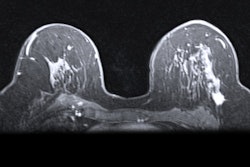

Multiparametric MRI helps predict breast cancer treatment response, according to a report on the RSNA's Breast Multiparametric MRI for prediction of neoadjuvant chemotherapy Response (BMMR2) challenge published January 5 in Radiology: Imaging Cancer.

Neoadjuvant therapy is the standard method for treating breast cancer, and quantitative MRI metrics have "shown promise for predicting individual treatment outcome, which could aid in personalizing therapies," the authors wrote. In an effort to explore the efficacy of MRI for this indication, the RSNA held the BMMR2 challenge between May and December of 2021, asking participants to identify image-based markers taken from multiparametric breast MR imaging -- including diffusion-weighted imaging (DWI) and dynamic contrast-enhanced (DCE) MR imaging -- as well as clinical data (i.e., race, sex, HR2/HER2 subtype, lesion type) that could help predict whether a patient would have a complete response following neoadjuvant treatment. Eight teams participated.